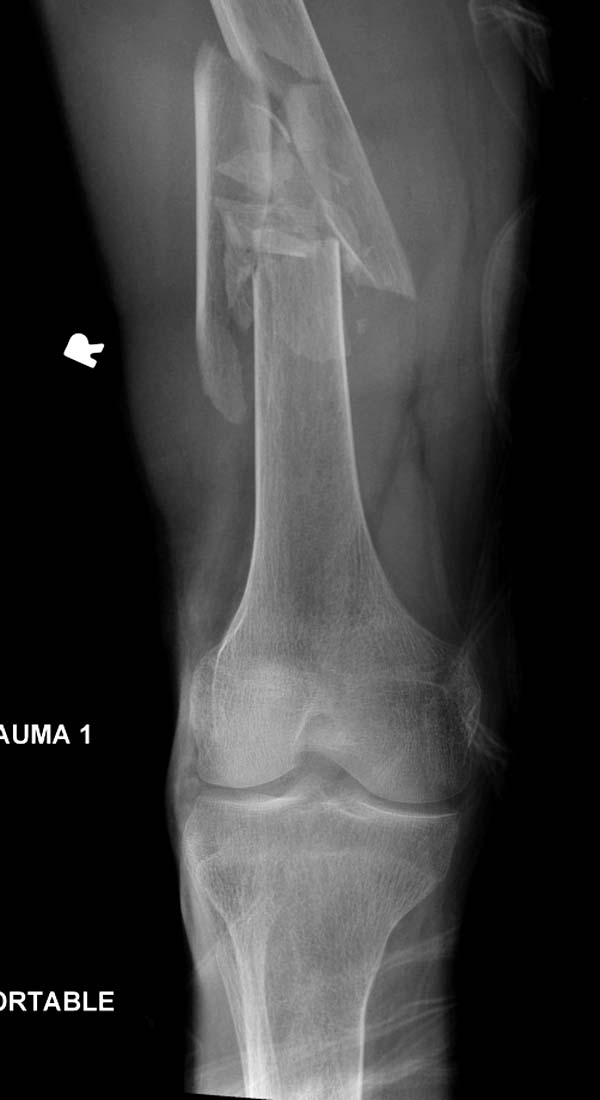

Больному 25 лет, транспортная травма. С детства хроническая почечная

недостаточность, постоянный гемодиализ, находится в листе ожидания на

пересадку почки. Около 4 года назад автоавария с двухсторенним переломом

ацетабулум, которая слева закончилось тотальным протезированием.

Диагноз: переломы бедренных костей, перелом дистального плеча слева,

также неосложненный перелом на уровне грудных позвонков.

Имя     : 1 Periprosthetic IM nail pelvis.jpg